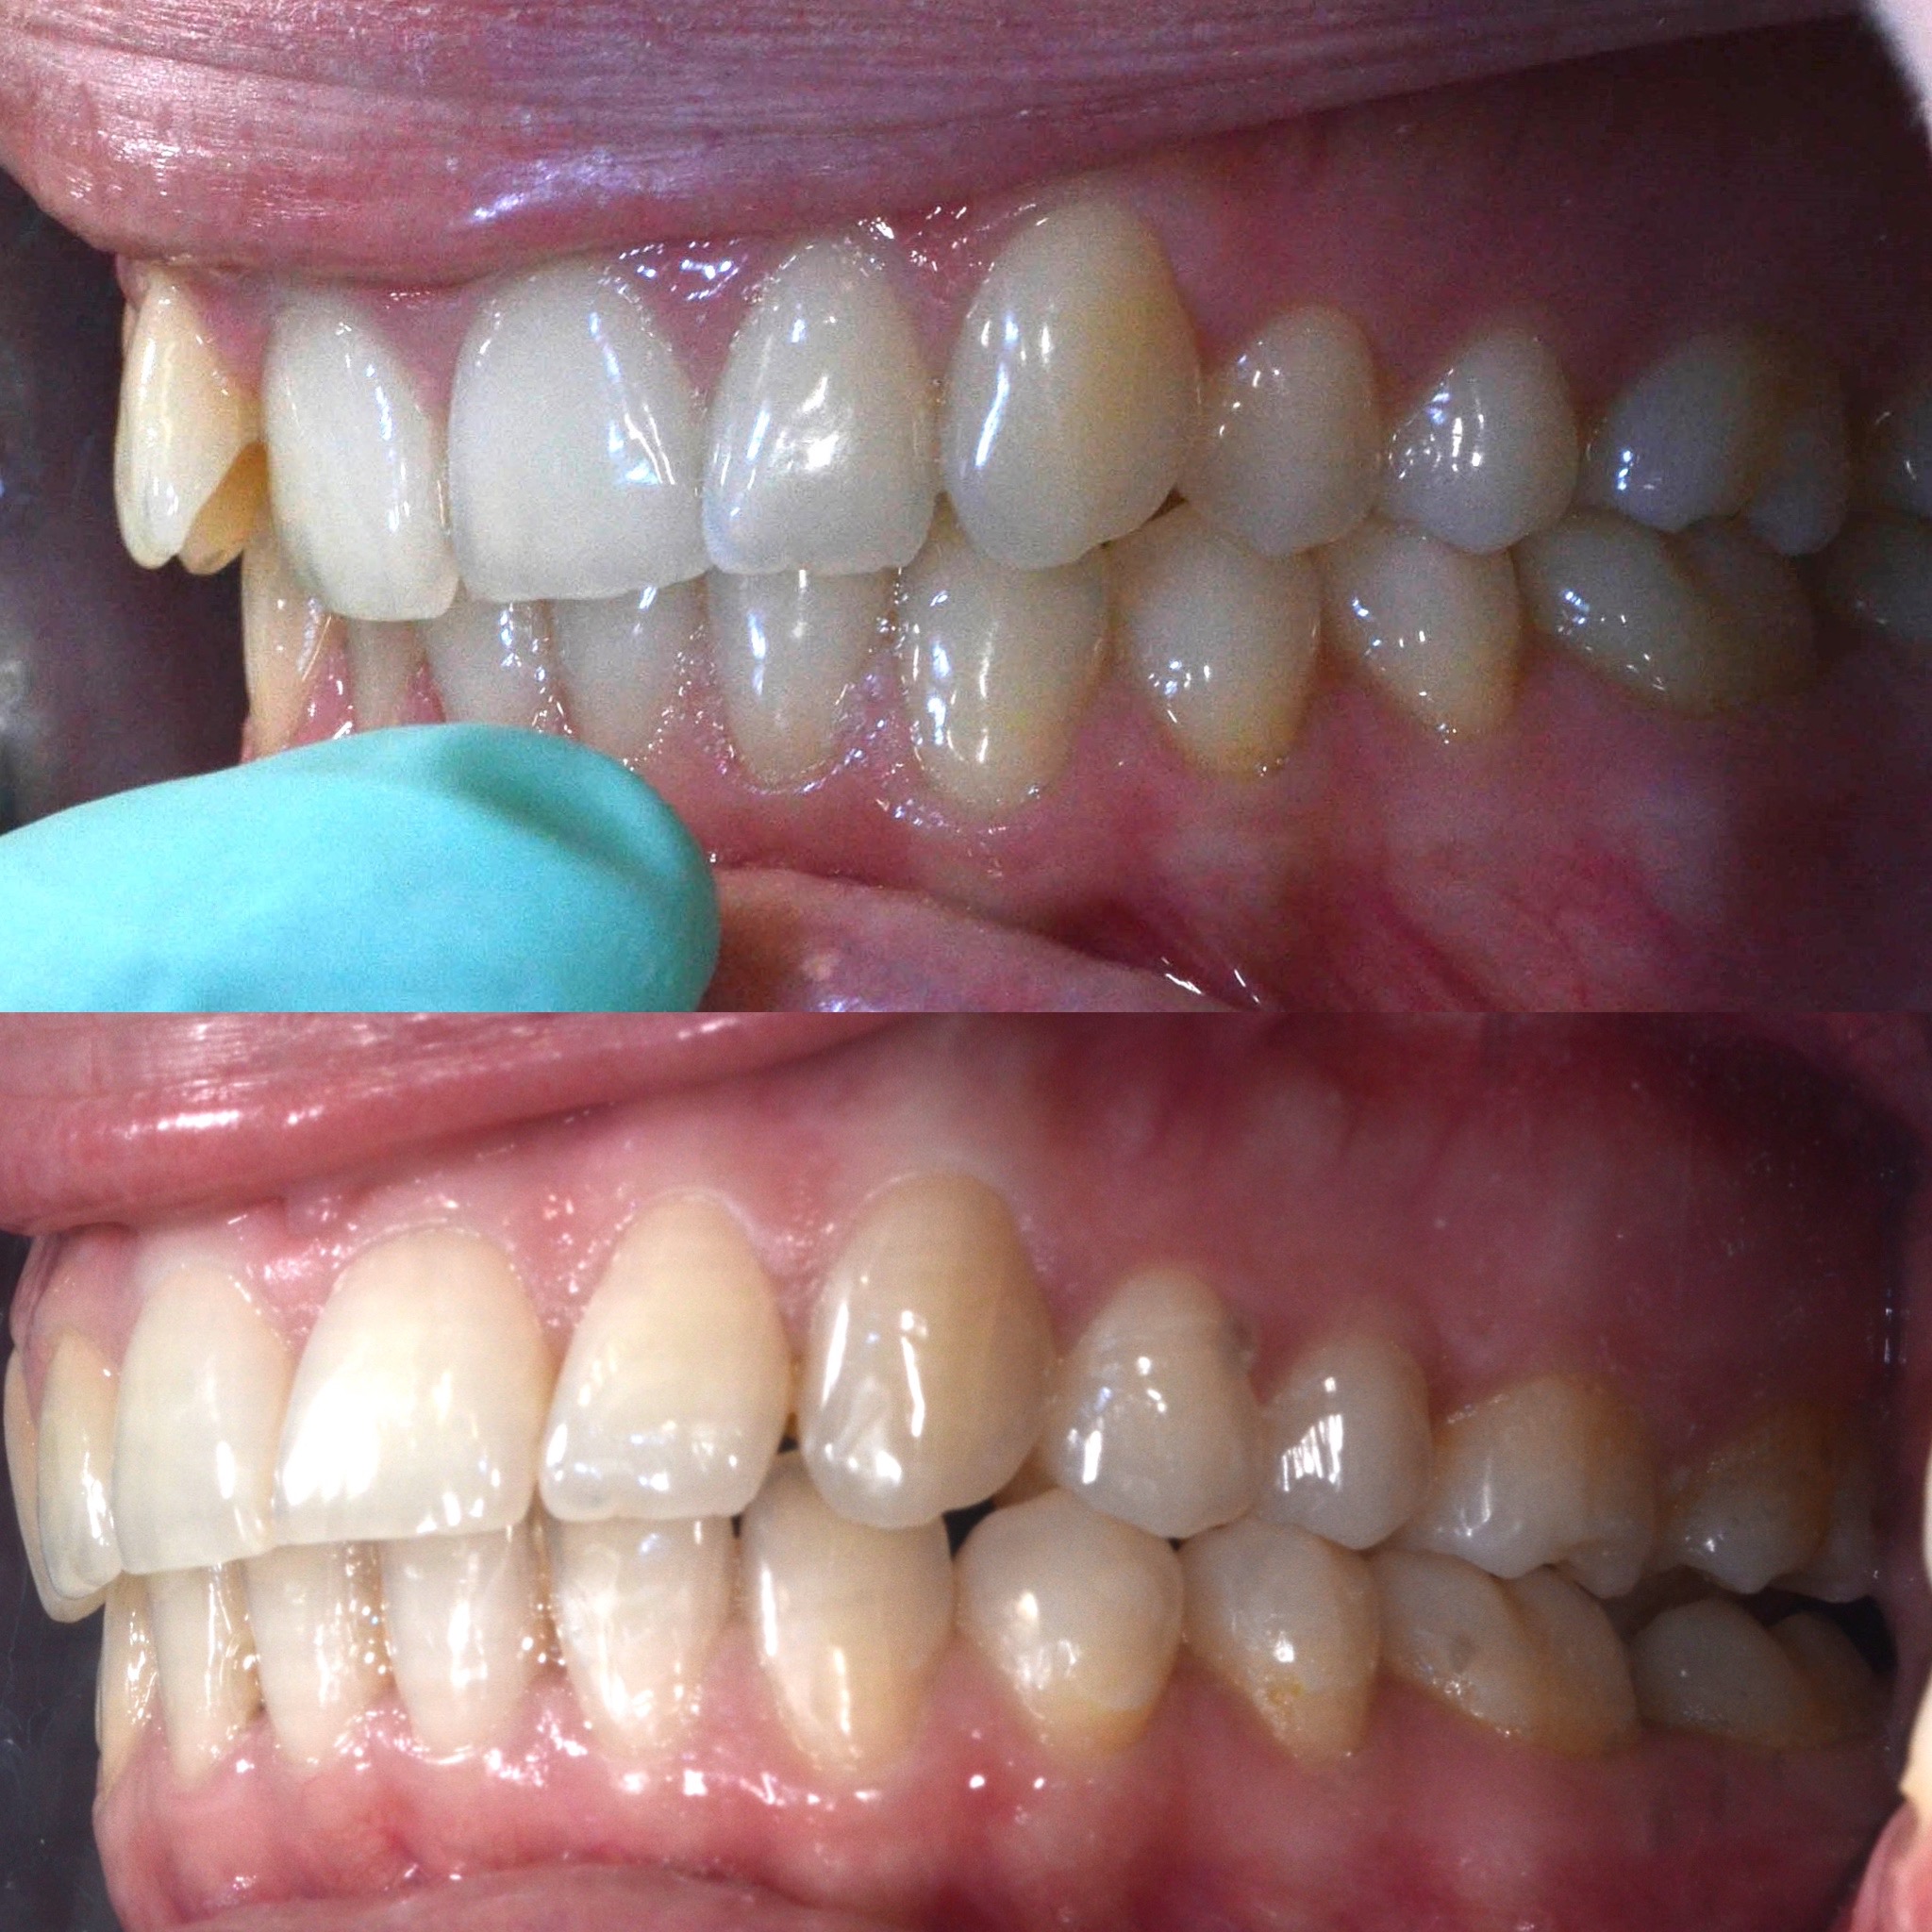

Slučaj 1: ispravljanje otvorenog zagriza i kompresije Invisalign full terapijom

Slučaj 2: ispravljanje kompresije Invisalign full terapijom- u ovom slučaju je izvađen jedan donji sjekutić

Slučaj 3: ispravljanje kompresije Invisalign full terapijom

Slučaj 4: ispravljanje kompresije Invisalign full terapijom

Slučaj 5: ispravljanje kompresije i križnog zagriza Invisalign full terapijom

Slučaj 6: ispravljanje kompresije i dubokog zagriza Invisalign full terapijom

Slučaj 7: ortodontska predprotetska terapija Invisalign full